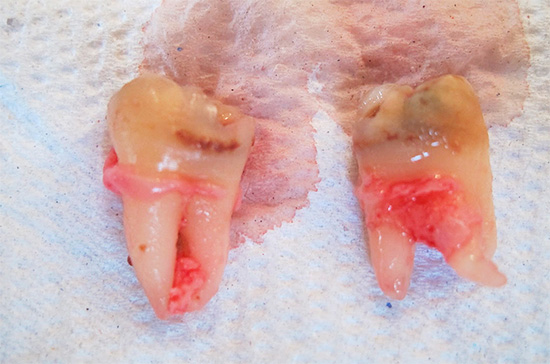

Foto dei denti del giudizio rimossi:

Nella foto - un dente del giudizio rimosso in alcune parti: